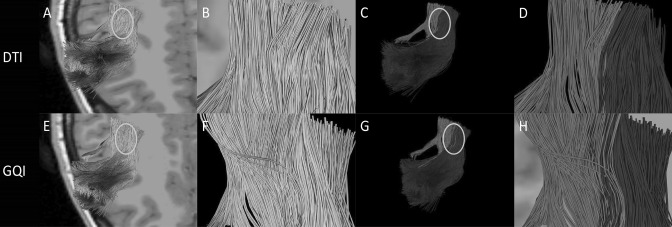

After reconstruction, we can get two different results in two reconstruction methods. Red shows the movement of the anterior part of arcuate fasciculus, blue shows the movement of the supplementary motor area (SMA) (Fig. 6). We present the results of the two reconstruction methods on an image for easy comparison analysis. After reconstruction by DTI, these two kinds of nerve fibers go in a parallel way and there is no obvious intersection in the path of the two nerve fibers (Fig. 6c, d). However, we can observe that there are a lot of intersecting areas between the two nerve fibers after reconstructed by GQI (Fig. 6g, h).

Fig. 6.

a Image of arcuate fasciculus and the supplementary motor area (SMA) reconstructed by DTI. The circle is the crossing region for the SMA and the anterior part of arcuate fasciculus. b A close-up view of the circled section in a. c Different tracts are marked with different colors: the anterior part of arcuate fasciculus is shown in red, the SMA is shown in blue. The position of the circle is the area where the two tracts of fibers intersect. d A close-up view of the circled section in C. e Image of arcuate fasciculus and the SMA reconstructed by GQI. The circle is the crossing region for the SMA and the anterior part of arcuate fasciculus. f A close-up view of the circled section in e. g Different tracts are marked with different colors: the anterior part of arcuate fasciculus is shown in red, the SMA is shown in blue. The position of the circle is the area where the two tracts of fibers intersect. h A close-up view of the circle section in g (color figure online)